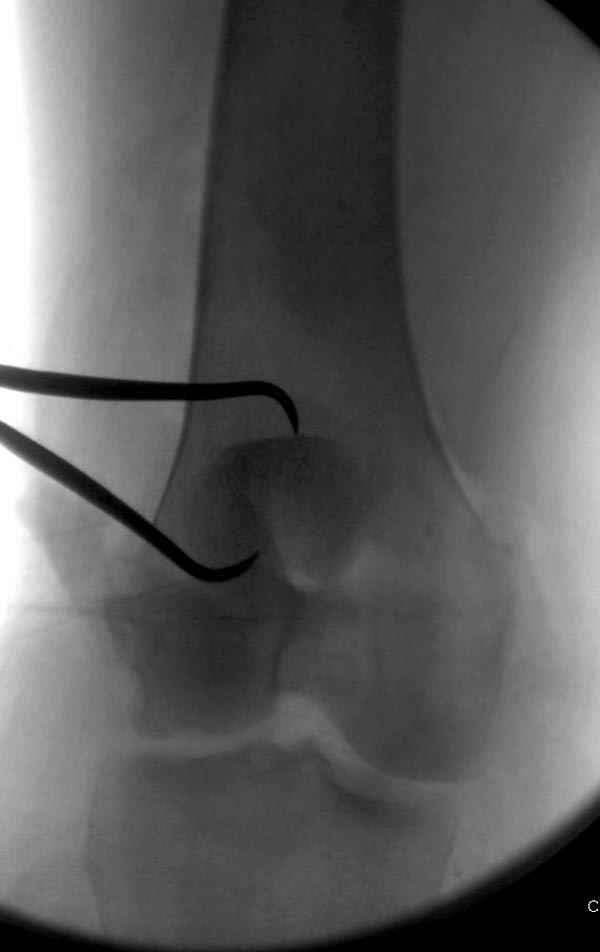

Сегодня досылаю остальные снимки, которые не прошли вчера. Как вчера писал, после фиксации перелома надколенника с дефектом кости и собственной связки, наложили ваккуум и наружный фиксатор. (снимки 4-9)

Внешний фиксатор держим около 6 недель, поэтому был выбран метод фиксации шурупами и еще линия перелома была диагональной, не было нужды в tension band technique, cannulated screws удобнее, провел спицы и по ним шурупы.

Связка ушита обычными сухожильными швами конец в конец, не было нужды проведения шва через надколенник, из-за ех-фиксатора.

Внешний фиксатор снимаем за пару недель до пластики крестообразных связок, мой партнер специалист по спортивной травме, считает оптимально в 6-8 недель, только не могу догадаться, чем будет производить пластику поврежденной собственной связки?